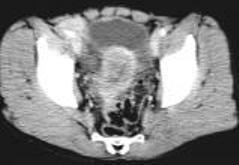

病历摘要:男,54岁病史:间歇性肉眼血尿伴下腹部隐痛7月余。为全程血尿,浓茶色,并有尿频尿急尿痛。当地医院曾造影检查示“膀胱结石”,入院前3天当地医院检查示“膀胱肿瘤”体查:心肺腹无明显阳性体征,双肾区无叩痛,双输尿管行程无压痛点,膀胱区未见肿胀、隆起实验室检查:尿常规:淡黄色,混浊,潜血大量,镜检白细胞370/μl(↑)